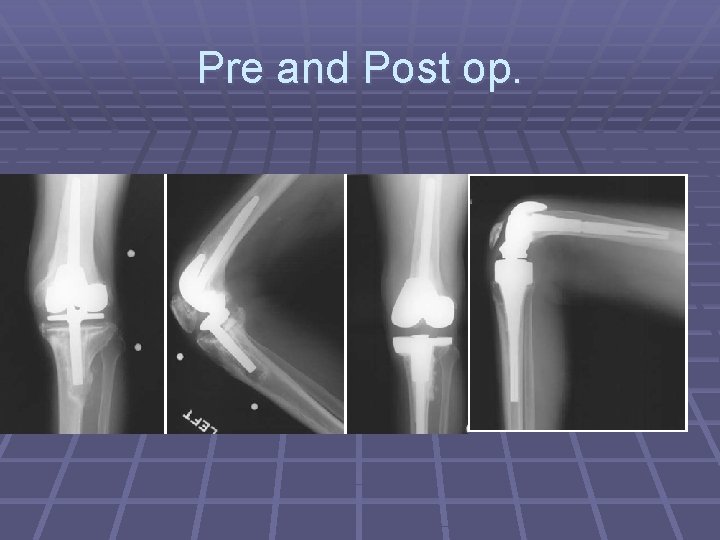

Pre and Post op.

RESULTS OF REVISION KNEE ARTHROPLASTY § The clinical results of revision TKA are not as good as the results of primary arthroplasty § Series with at least 5 years follow-up reported good to excellent results in 46% to 74% of patients. § 22% (6 of 27) reoperation rate at 9. 8 years postoperatively

RESULTS OF REVISION KNEE ARTHROPLASTY Cont. § Deep infection rate 4. 5% in revision arthroplasties followed for 5 years, repeat revision follow-up of 7. 5 years, reported a 20% infection rate , are significantly more frequent than after primary TKA which is 1. 6% to 2. 5% § Complications of the extensor mechanism reoperation was necessary in 41% § Aseptic loosening, wound problems, and tibiofemoral instability